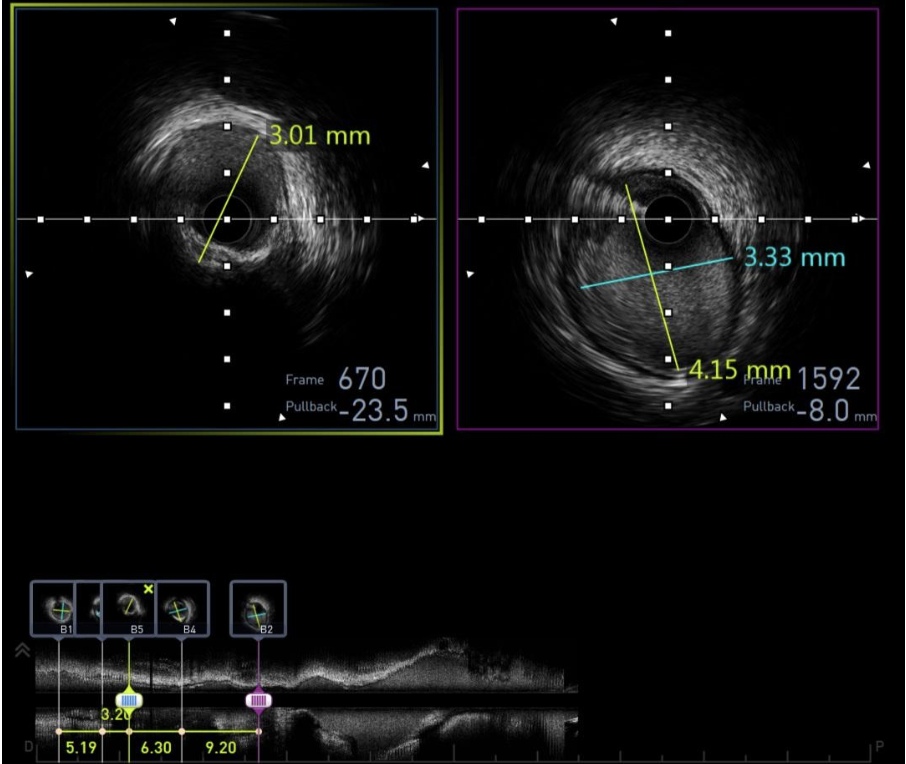

Đo kích thước mạch vành đoạn gần và đoạn xa nhằm chọn kích thước stent và bóng nong phù hợp

🔹 Đo kích thước lòng mạch thực tế, tăng tính an toàn can thiệp.